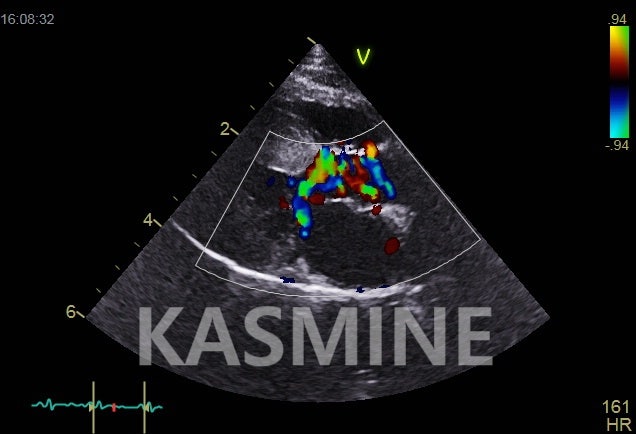

어쨌든 다시 본론으로 들어가서 전북대병원에서는 심장 초음파 시잔이 1시간 반이나 걸렸고, 아무것도 모르는 강아지는 낯선 곳에서 정말 힘들어했다.

이번에도 심장 초음파를 찍는다면 9월에 진단을 받은 뒤 올 11월까지 심장 초음파를 4번이나 찍은 셈이다.

사실 화요일에 같은 임상증상이 있어서 심장초음파를 찍고 싶었는데 이런 상황을 양 선생님께서 말씀을 드리면 이해해주시고

기본검사 먼저 해보고 화요일 빼고는 안정적으로 유지되고 있기 때문에 우선 기본혈압 등을 재보겠다고 하셨다.

폐동맥 혈압과 전체 혈압은 다르지만 혈압도 전에 내원했을 때보다 안정적으로 낮아지고 활력징후가 괜찮다고 하셨다.